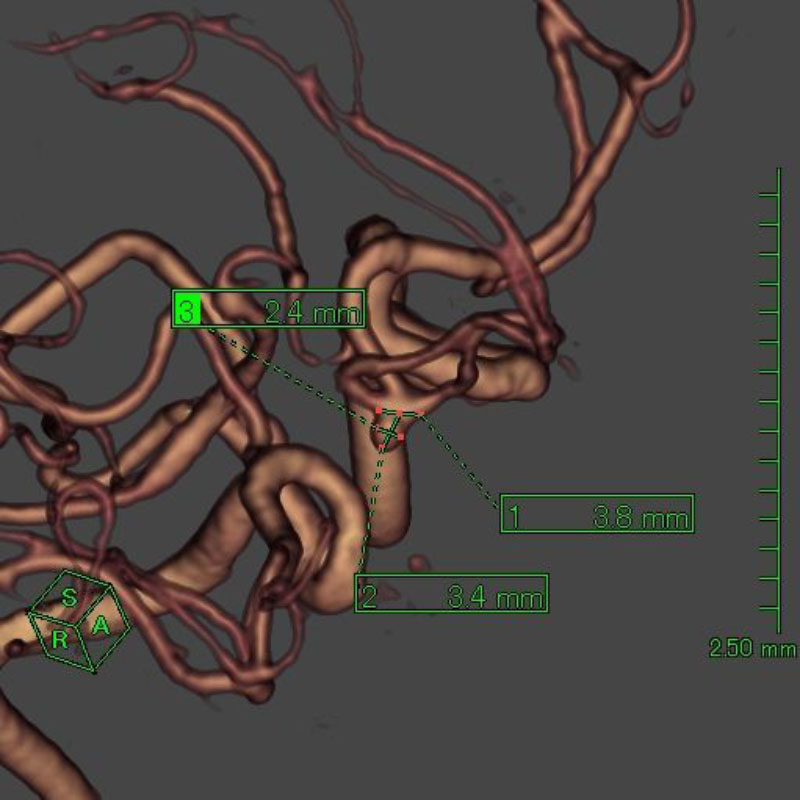

病名(部位)

術式

手術前

クリップ前

クリップ後

手術後